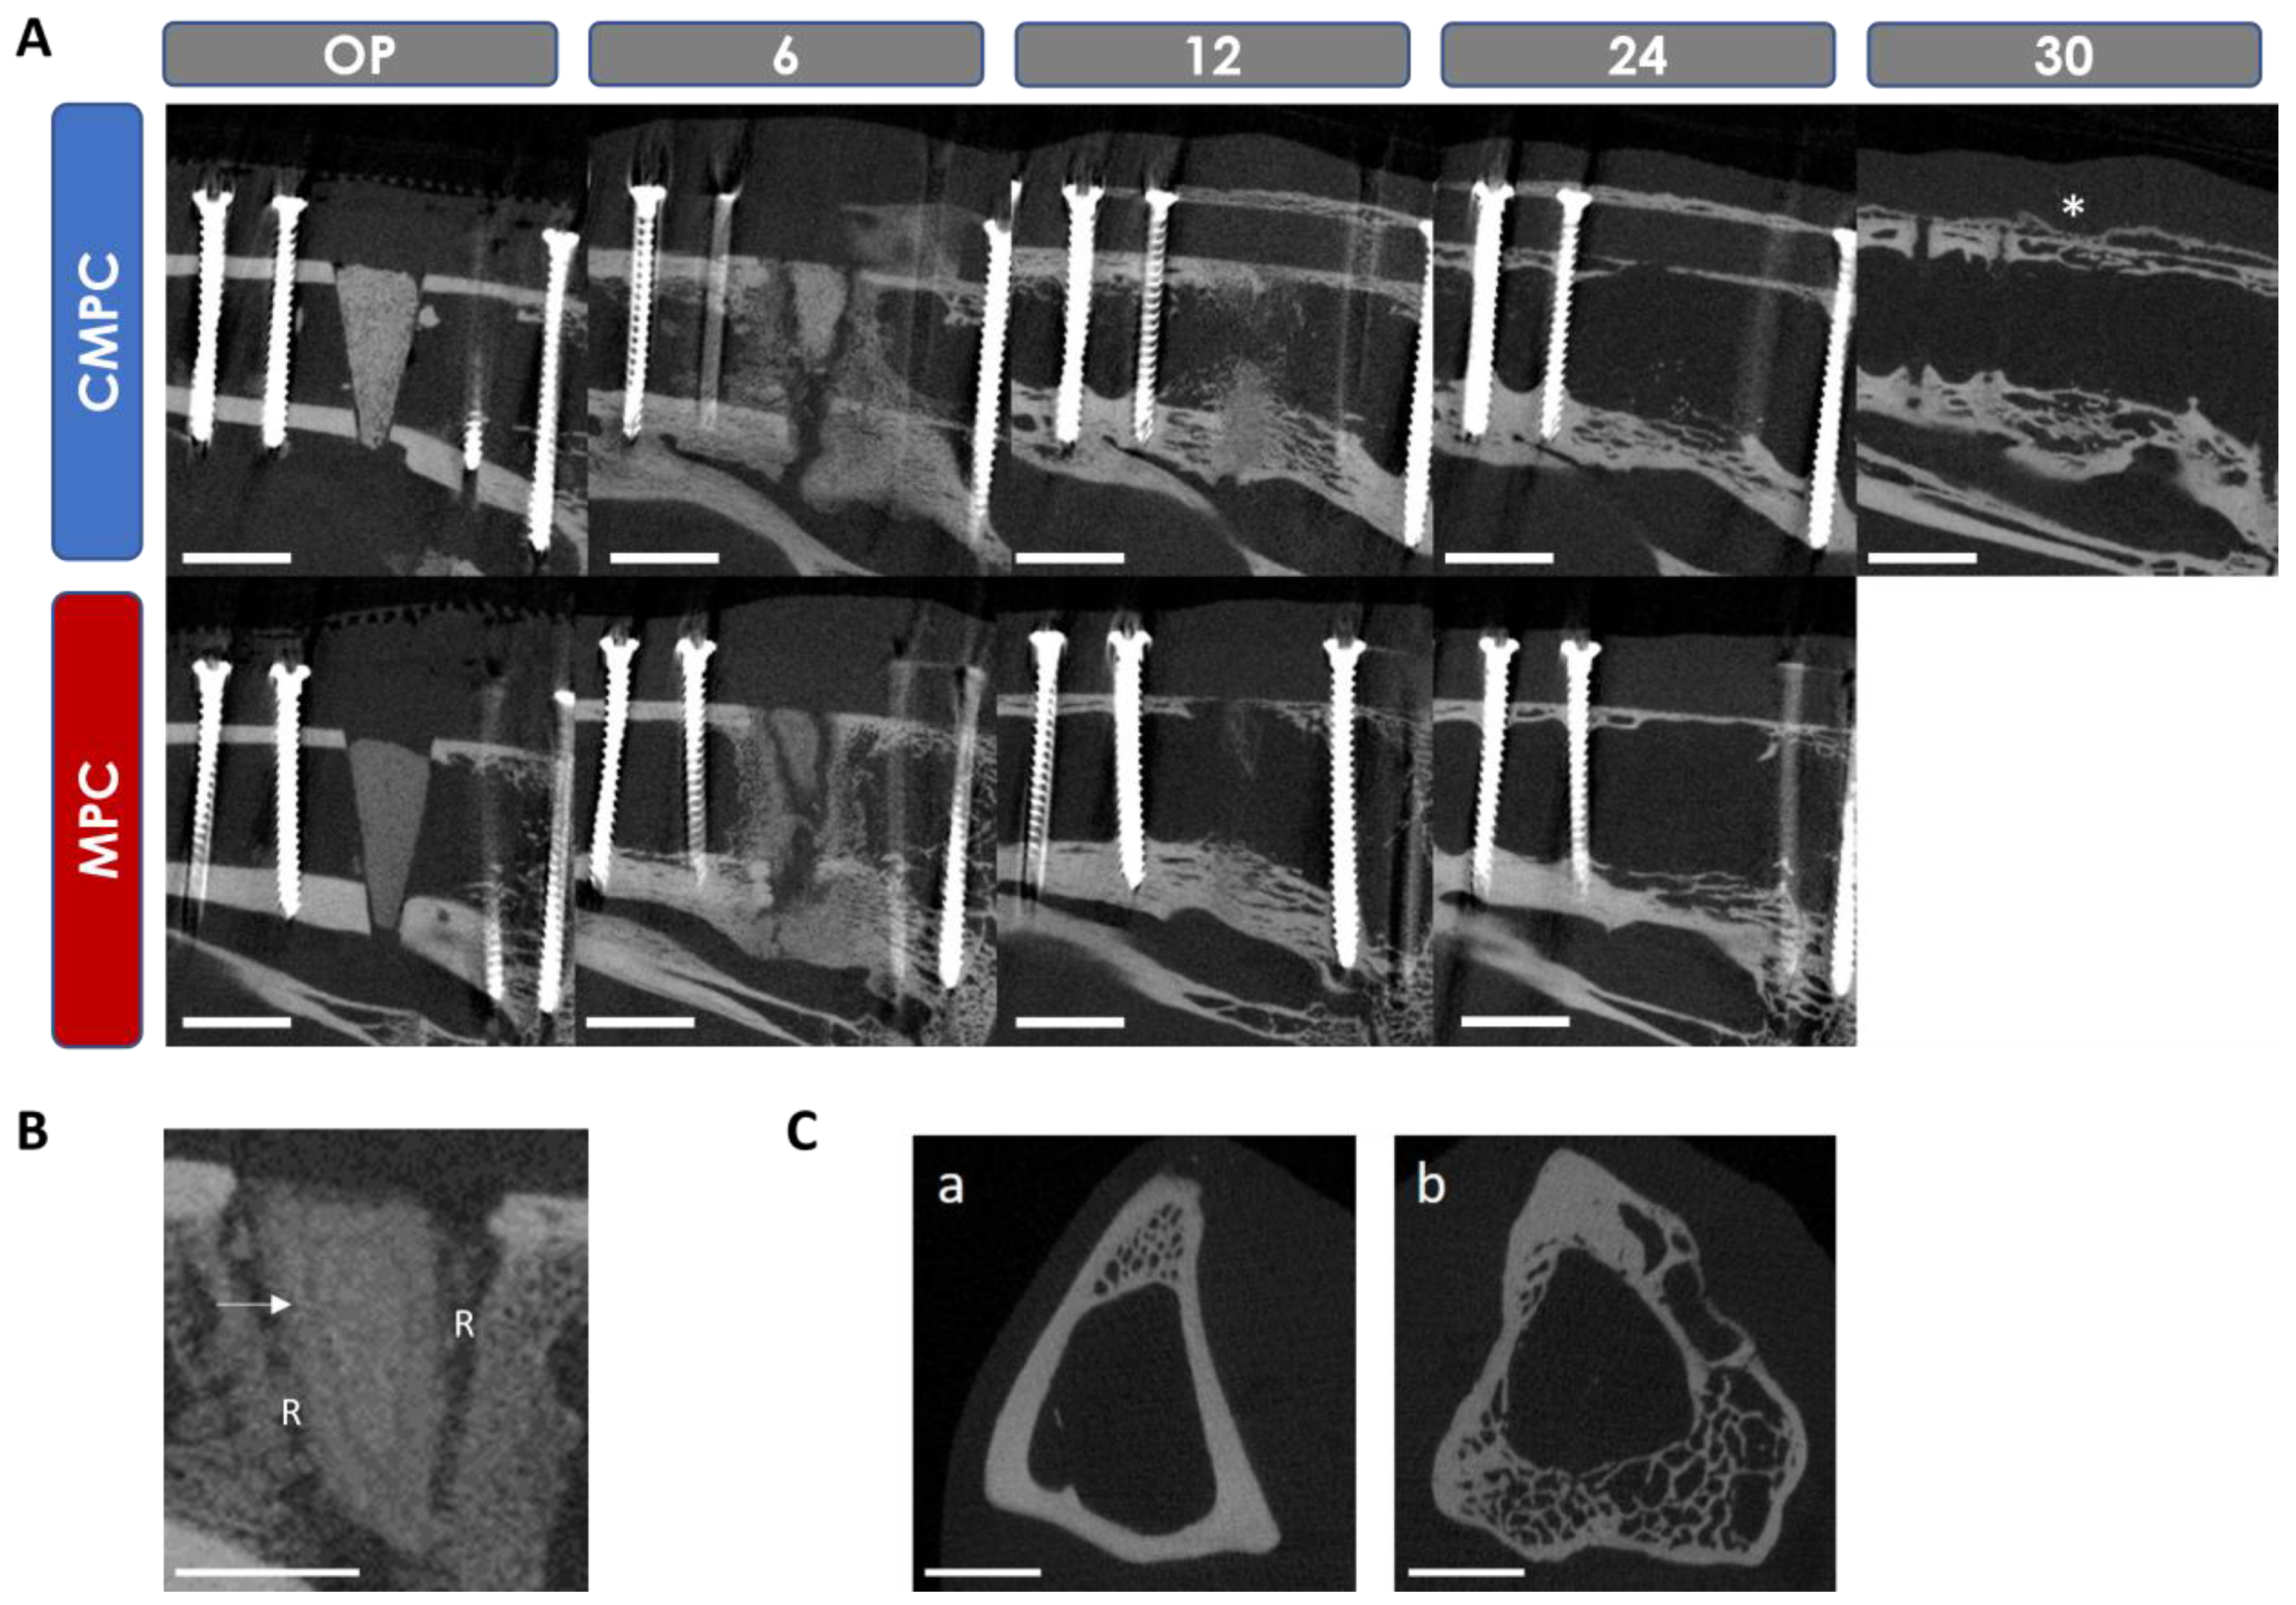

3.5. In Vivo µCT Examinations

3.5.1. Semi-Quantitative Evaluation of the Scans

3.5.2. Quantitative Evaluation of the Scans